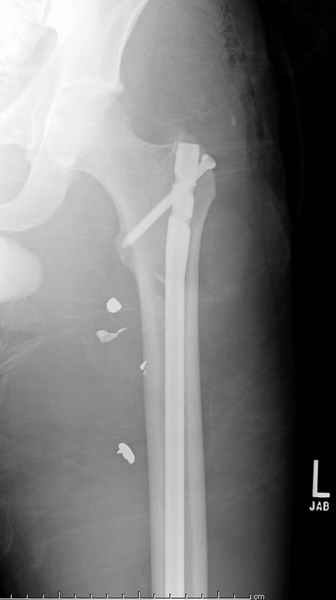

Больной с огнестрельным переломом бедра с вовлечением около 15% медиального кортекса, входное отверстие около 1 см в диаметре; стабильный, без сосудистых и неврологических признаков.

Учитывая, что больной получил травму не во время визита в церковь, и он является одним из представителем 40 миллионного “outstanding itizen”, без медицинской страховки, без работы в свои 39 лет, и без надлежающей ортопедической дисциплины у которого отсутсвует страх стрессового перелома, было рекомендовано оперативное лечение: профилактическое антеградное интрамедуллярное штифтование.

Методика штифтования при отсутствии большой зоны перелома как при онкологических профилактических штифтованиях, расверливание интрамедуллярного канала проводим с предварительным наложением дополнительного дренажного отверстия в дистальном отделе бедра (в данном случаи в канале оставили 6.5 мм канюлированный шуруп), иначе при создании давления в канале во время сверления имеется опасность эмболизации легочной артерии тромбом.